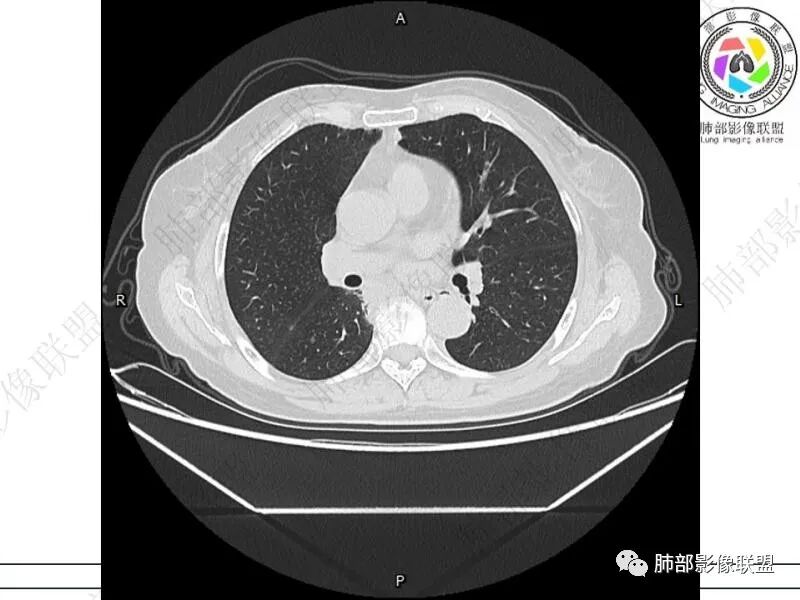

丽:双肺下叶胸膜下多发片状高密度影,边缘模糊不清,内可见支气管穿行,病变长轴平行于胸膜,考虑感染性病变,隐球菌

谢加平:结肠癌术后史,两肺胸膜下多发结节及斑块实变病灶,实边边界平直征(亚急性和慢性病变过程),双肺下叶后基底段胸膜下为甚,与胸膜平行特点,见支气管充气征,边缘模糊的GG0,首诊2022年11月18日肺部CT,与治疗11月28日对比,病灶未吸收,双肺下叶胸膜下病灶有侧向融合特点,综合分析符合炎性肉芽肿,隐球菌感染。

老年女性,结肠癌术后。两下肺胸膜下为主片状实变,右下肺短期复查融合且病灶长轴平行于胸膜,实变内可见支气管充气征,边缘磨玻璃晕,另两肺内胸膜下散在数枚小结节状、楔形实性灶。考虑感染性病变,隐球菌可能,鉴别肺转移。

2.影像特征:双肺胸膜下多发实性结节、磨玻璃影及实变影,胸膜下优势分布、晕征、胸膜下脂肪间隙存在,部分病灶边界平直征,有侧向融合趋势。